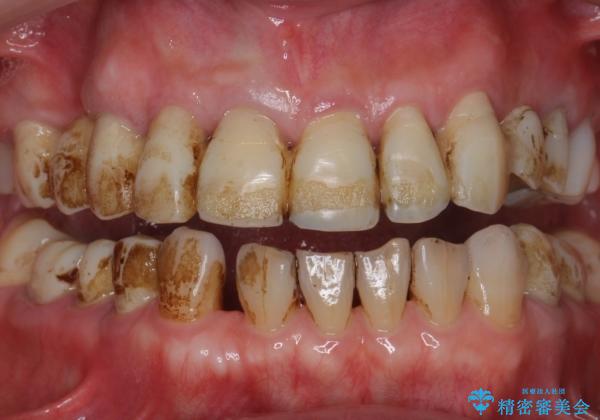

べったり付着した、ステインや汚れをきれいに。

- 日頃からコーヒーをよく飲むそうでべったりとステインが付着していました。

ステインがたくさん付着していたので、エアフローを用いてステインを除去しました。そのため、直後の写真は歯肉からの出血が見られます。